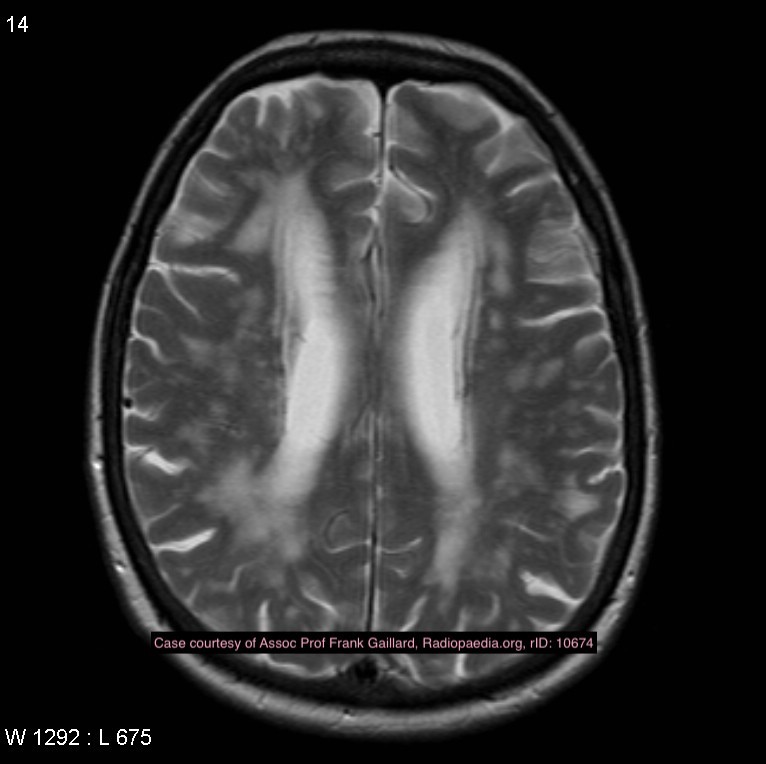

Case courtesy of Assoc Prof Frank Gaillard, Radiopaedia.org. From the case rID: 10674

Vascular dementia

Case Discussion

MRI demonstrates prominent deep white matter T2 hyperintensity with resultant central volume loss. There is no lobar atrophy, suggesting the dementia is likely due to multiple white matter infarcts.